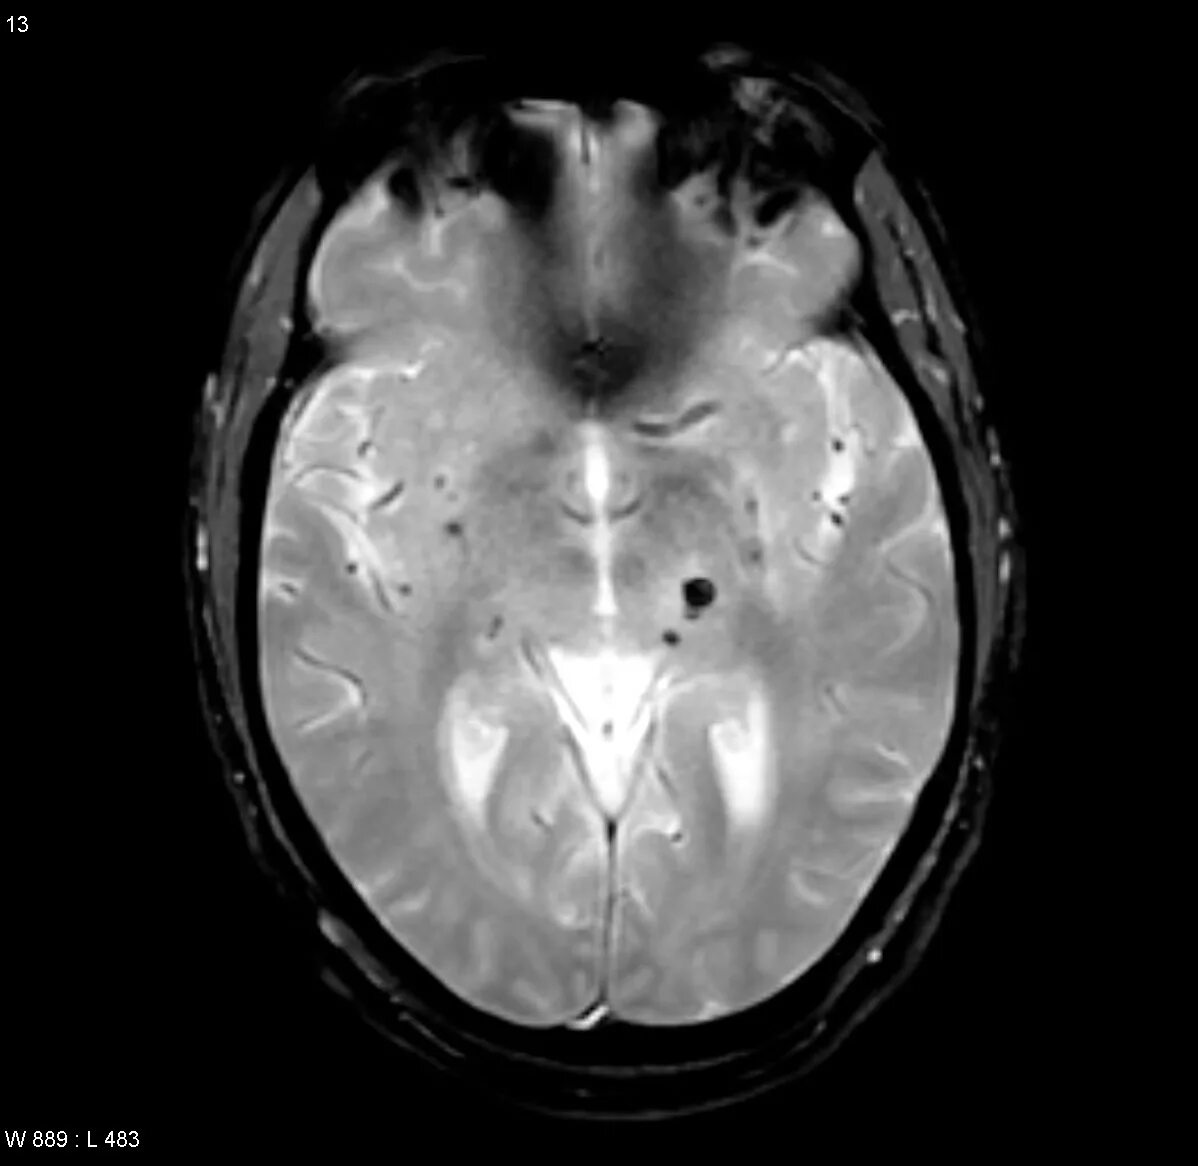

Микроангиопатия головного мозга симптомы